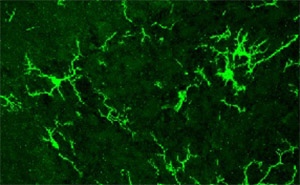

Foto de microscopía de células microgliales que responden a estímulos inflamatorios en el cerebro y liberan moléculas que pueden afectar el funcionamiento de las neuronas. (Foto: DICYT)

Para entender el mecanismo involucrado, los investigadores estudiaron en los roedores el efecto de la exposición prenatal a VPA sobre la activación de las células de la glía: aquellas que se encargan de dar sostén a las neuronas y defienden al cerebro del daño. Los resultados fueron sorprendentes: observaron signos de inflamación sólo en la crías hembras, las “protegidas”, pero no en los machos.

“La glía podría mediar mecanismos compensatorios que eviten que se afecten las neuronas que regulan la sociabilidad”, interpretó Depino.